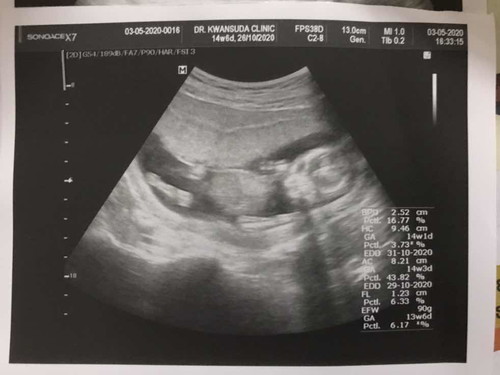

14 สัปดาห์ 6 วัน

แม่ๆท่านอื่น ซาวน์น้องแล้วรู้เพศบ้างยังคะ คุณหมอบอกน่าจะเป็นผู้หญิงค่ะ นัดครั้งหน้าถึงจะรู้เพศที่ชัดเจน